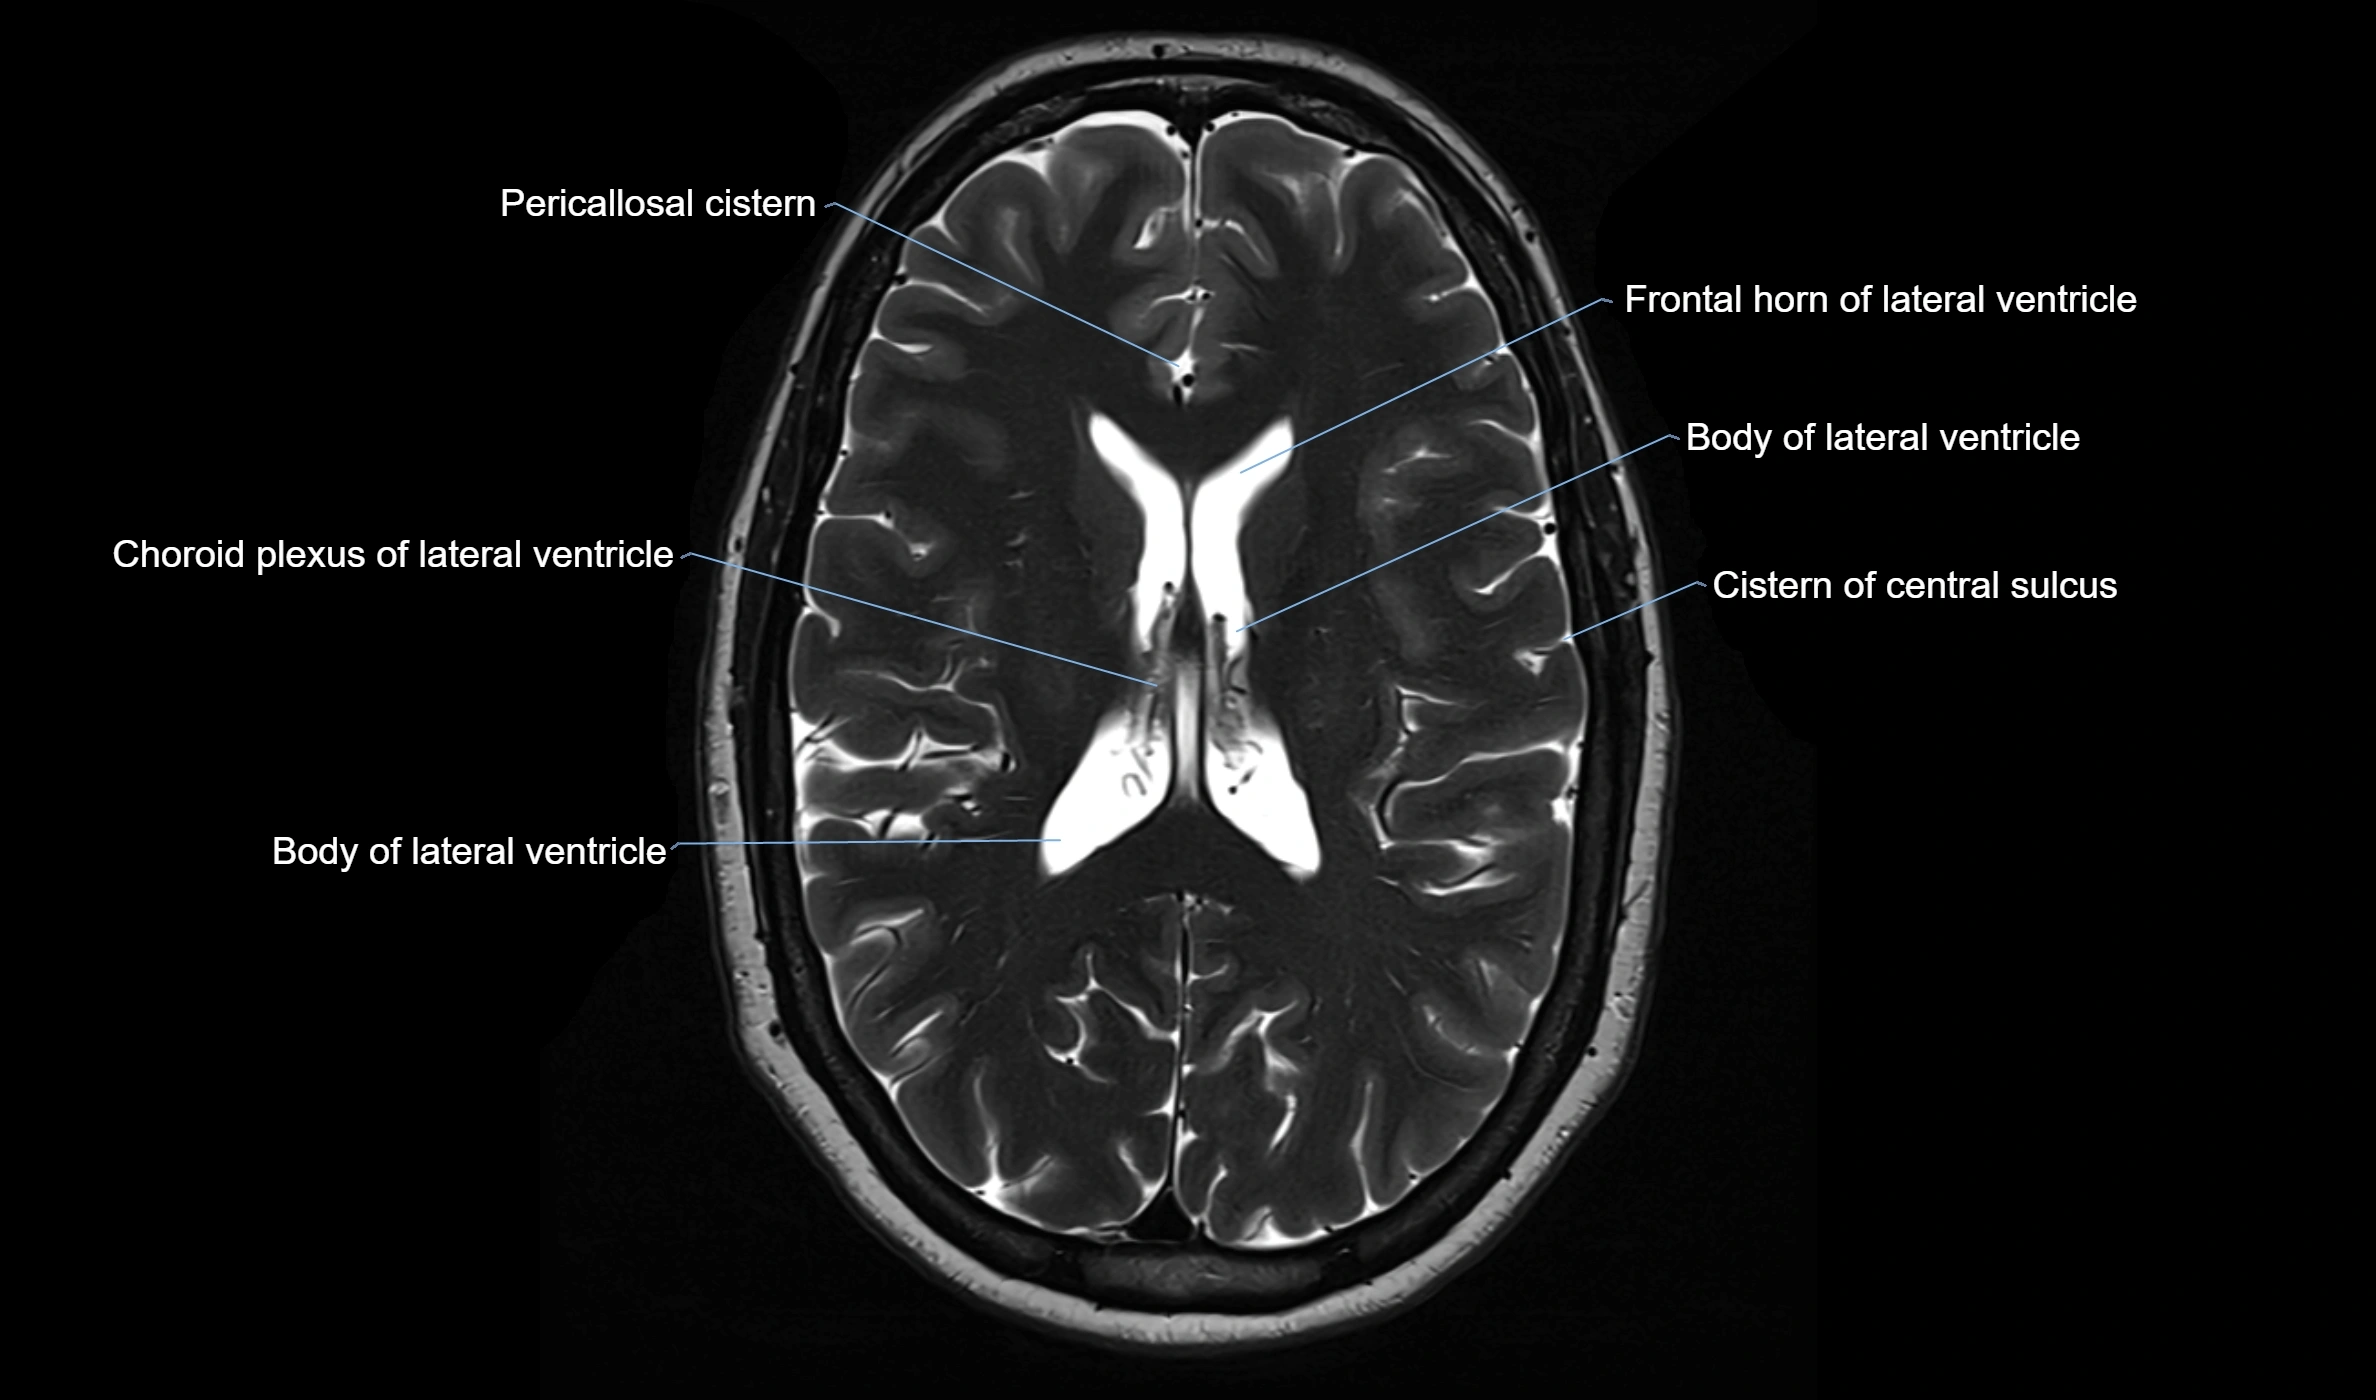

CT image

image